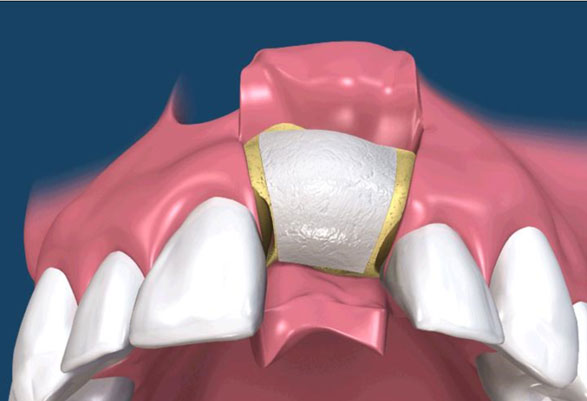

骨粉合併再生膜

在 GTR 及 GBR 技術中所使用的阻隔膜是用來將缺損的區域分開成兩個隔間。 GTR 技術的目的是再生完全俱功能的牙周膜,包含新的牙骨質、牙周韌帶(PDL)及新骨。GBR 技術的目的是再生新骨,對此,細胞從下層的骨組織需要分佈至缺損處。(圖09-12)